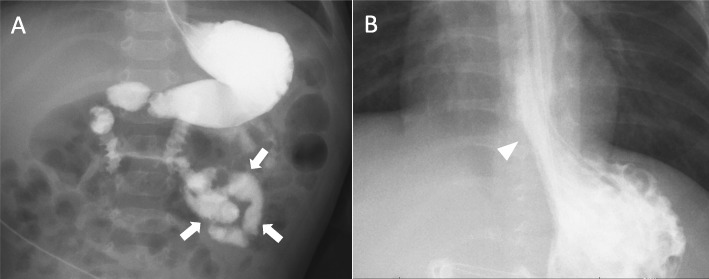

Intestinal malrotation was diagnosed after the patient began experiencing recurrent vomiting started at 6 months of age (Fig. 1a). The volvulus was successfully relieved by surgery. However, the vomiting signs persisted beyond the surgical repair due to the presence of another digestive dysfunction, gastroesophageal reflux (Fig. 1b). Although duodenal tube feeding was introduced, only limited amounts of nutrition could be provided, which proved insufficient to achieve weight gain during the 12-month follow-up period. Thus, tulobuterol (0.2 mg/day) was given orally from 12 months. The patient’s vomiting disappeared immediately after tulobuterol treatment, and his weight continued to increase until the time of writing this report. In the last month, it reached 5300 g (+ 300 g). Patients on peritoneal dialysis are also known to develop thyroid dysfunctions [6]. We verified that serum thyroid stimulating hormone (2.70 μIU/mL) and free thyroxine (1.48 ng/dL) levels remained unaltered. We thus did not interpret hyper- or hypothyroidism as a primary cause of his gastrointestinal problems.

Fig. 1.

Gastrointestinal phenotypes associated with Pierson syndrome. a An upper gastrointestinal contrast study depicting the intestinal malrotation. Arrows indicate the “corkscrew sign” of the proximal jejunum. b A radiographic contrast image depicting the gatroesophageal reflux (arrow head)